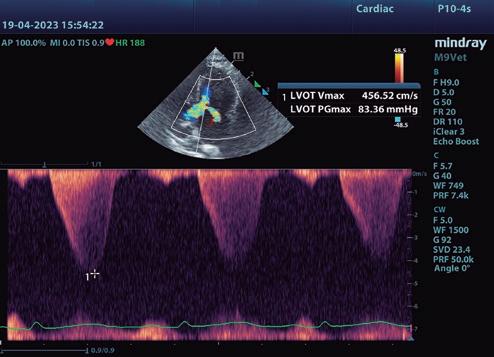

• Modo B: en la proyección paraesternal derecha eje largo, se observó un jet de regurgitación mitral con dirección posterior y SAM (figura 3). En el eje corto derecho a la altura de la base cardiaca se observó un ratio atrio izquierdo/aorta (AI/Ao) de 1,92 (>1,6 se considera dilatación AI) (figura 4). Además, se observó hipertrofia de la pared del septo interventricular (SIV) de 7,6 mm y la pared libre del ventrículo izquierdo (PLVI) la 8,4 mm (hipertrofia >6 mm) (figura 5).

• Modo M: en paraesternal derecho eje corto a nivel de músculos papilares se observó un aumento del grosor del SIV en sístole (SIVs) de 7,8 mm (hipertrofia >6 mm), así como una hipertrofia de los músculos papilares (figura 6). • Modo Doppler: en la proyección paraesternal izquierda apical cuatro cámaras se midieron los flujos mitral (onda E 0,89 m/s y onda A 0,66 m/s) y subaórtico (4,56 m/s) (figura 7) ambos turbulentos, pero con velocidades dentro de rango. Presencia de ODTSVI. El flujo dentro de la aurícula izquierda estaba ligeramente disminuido (0,23 m/s, rango <0.25 m/s), aunque sin smoke

7. Proyección paraesternal izquierda cinco cámaras. Mediante Doppler color, se observa el flujo turbulento hacia el TSVI y hacia el AI. Se toma la velocidad del flujo que discurre a través del TSVI, generando un gradiente de presión de 83,36 mmHg.

8. Proyección optimizada para la aurícula izquierda. En ella, se toma una de las varias medidas del flujo de sangre a este nivel para evaluar la predisposición del animal a sufrir un proceso trombótico (TEA).

Para el diagnóstico de fenotipo hipertrófico, la gold estándar es la ecocardiografía. Aunque no hay una medida mundialmente aceptada para un valor normal o anormal de grosor de la pared, un aumento focal o difuso por encima de 6 mm (Fuentes et al. 2020) confirma el diagnóstico. Un AI/ Ao >1,6, justifica la presencia de ICC. En nuestro caso, el diagnóstico de fenotipo hipertrófico, se sustenta por el aumento del grosor de la pared del VI (7,6 mm en modo B y 7,8 mm en modo M) y la ICC, por el del AI/Ao (1,92).

Determinamos un flujo transmitrálico pseudonormal por la presentación clínica, categorizando una disfunción diastólica moderada. Ante la falta del flujo venoso pulmonar y del Doppler tisular del anillo mitral (Schober y Chetboul 2015), es una suposición. Sería necesaria la toma de estas medidas para confirmarlo. El estudio REVEAL (Fox et al. 2018) no asocia un peor pronóstico al SAM, aunque revela que se trata de gatos diagnosticados más jóvenes, como es nuestro caso.